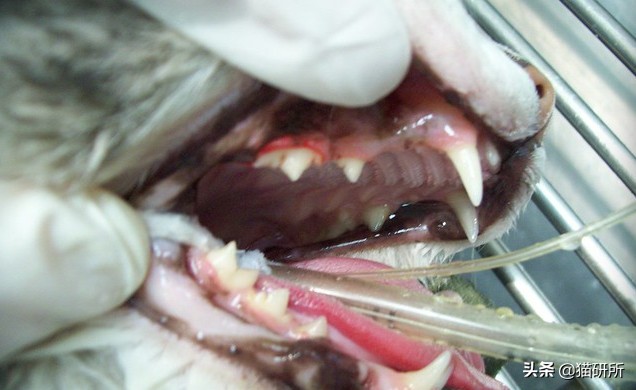

医生协助可观察到的症状

口腔检查可能因为患猫疼痛变得难于操作。图自:athealth.com

➤ 触诊可能发现肿大的下颌淋巴结。

➤ 可能看到牙龈和口腔黏膜会有不同程度的炎症、增生和溃疡。

➤ 非常严重的病例可能会由于增生导致咽部区域几乎完全阻塞。

需要注意的是:区别牙周病和口龈炎,关键在于口龈炎的病变区域发生在口腔的后部,并且通常是对称的。